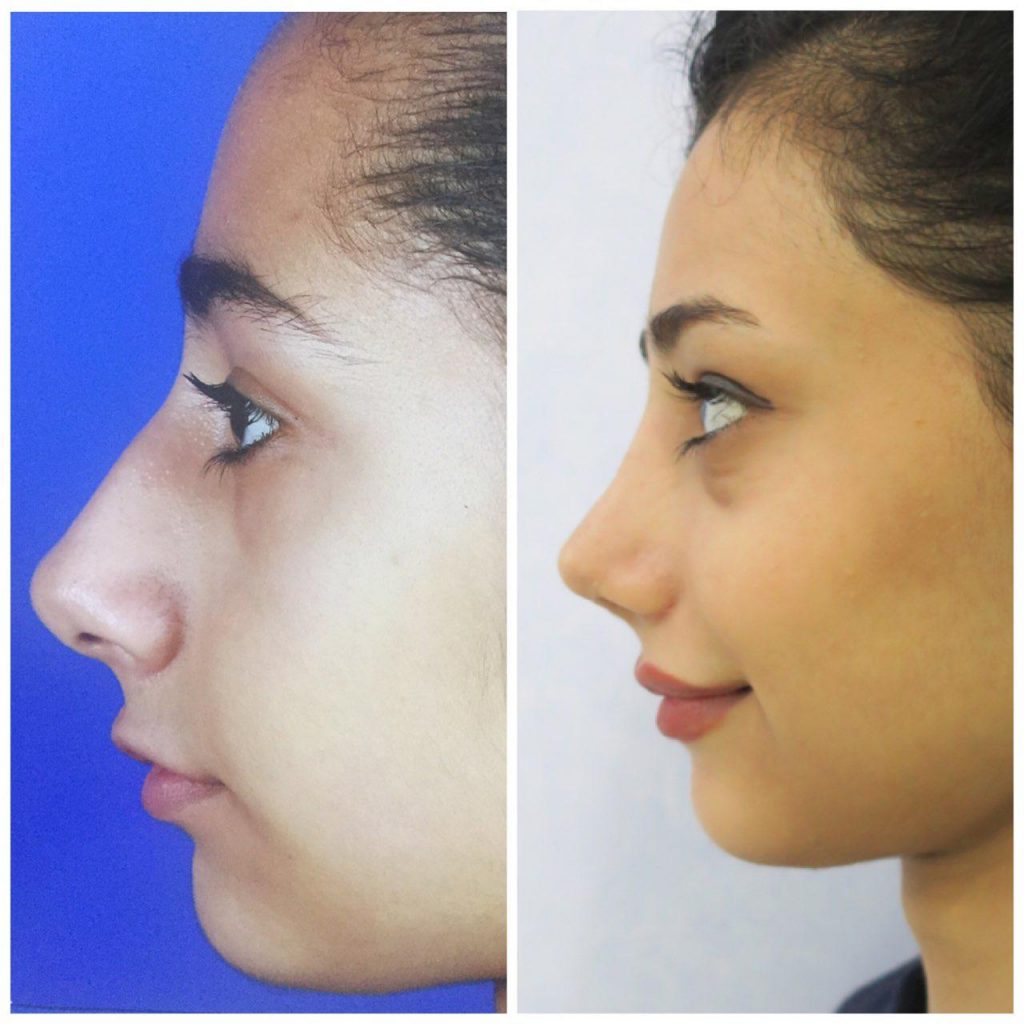

دکتر عیسی عبدی در رشت

دکتر عیسی عبدی در رشت

– متخصص جراحی فک , پلاستیک صورت و بینی

دکتر عیسی عبدی در رشت

جراحی فک , پلاستیک , صورت وبینی

جراحی ترمیمی و زیبایی فک و صورت و جمجمه و گردن